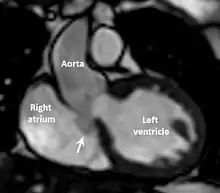

The first step in diagnosis is typically transthoracic echocardiography. However, if surgery is planned or if the standard echocardiogram lacks sufficient detail, then one or more additional studies are recommended. These studies include transesophageal echocardiography, 3D echocardiography, CT Angiography and aortic angiography.[4] Cardiac MRI may be another option.[2]